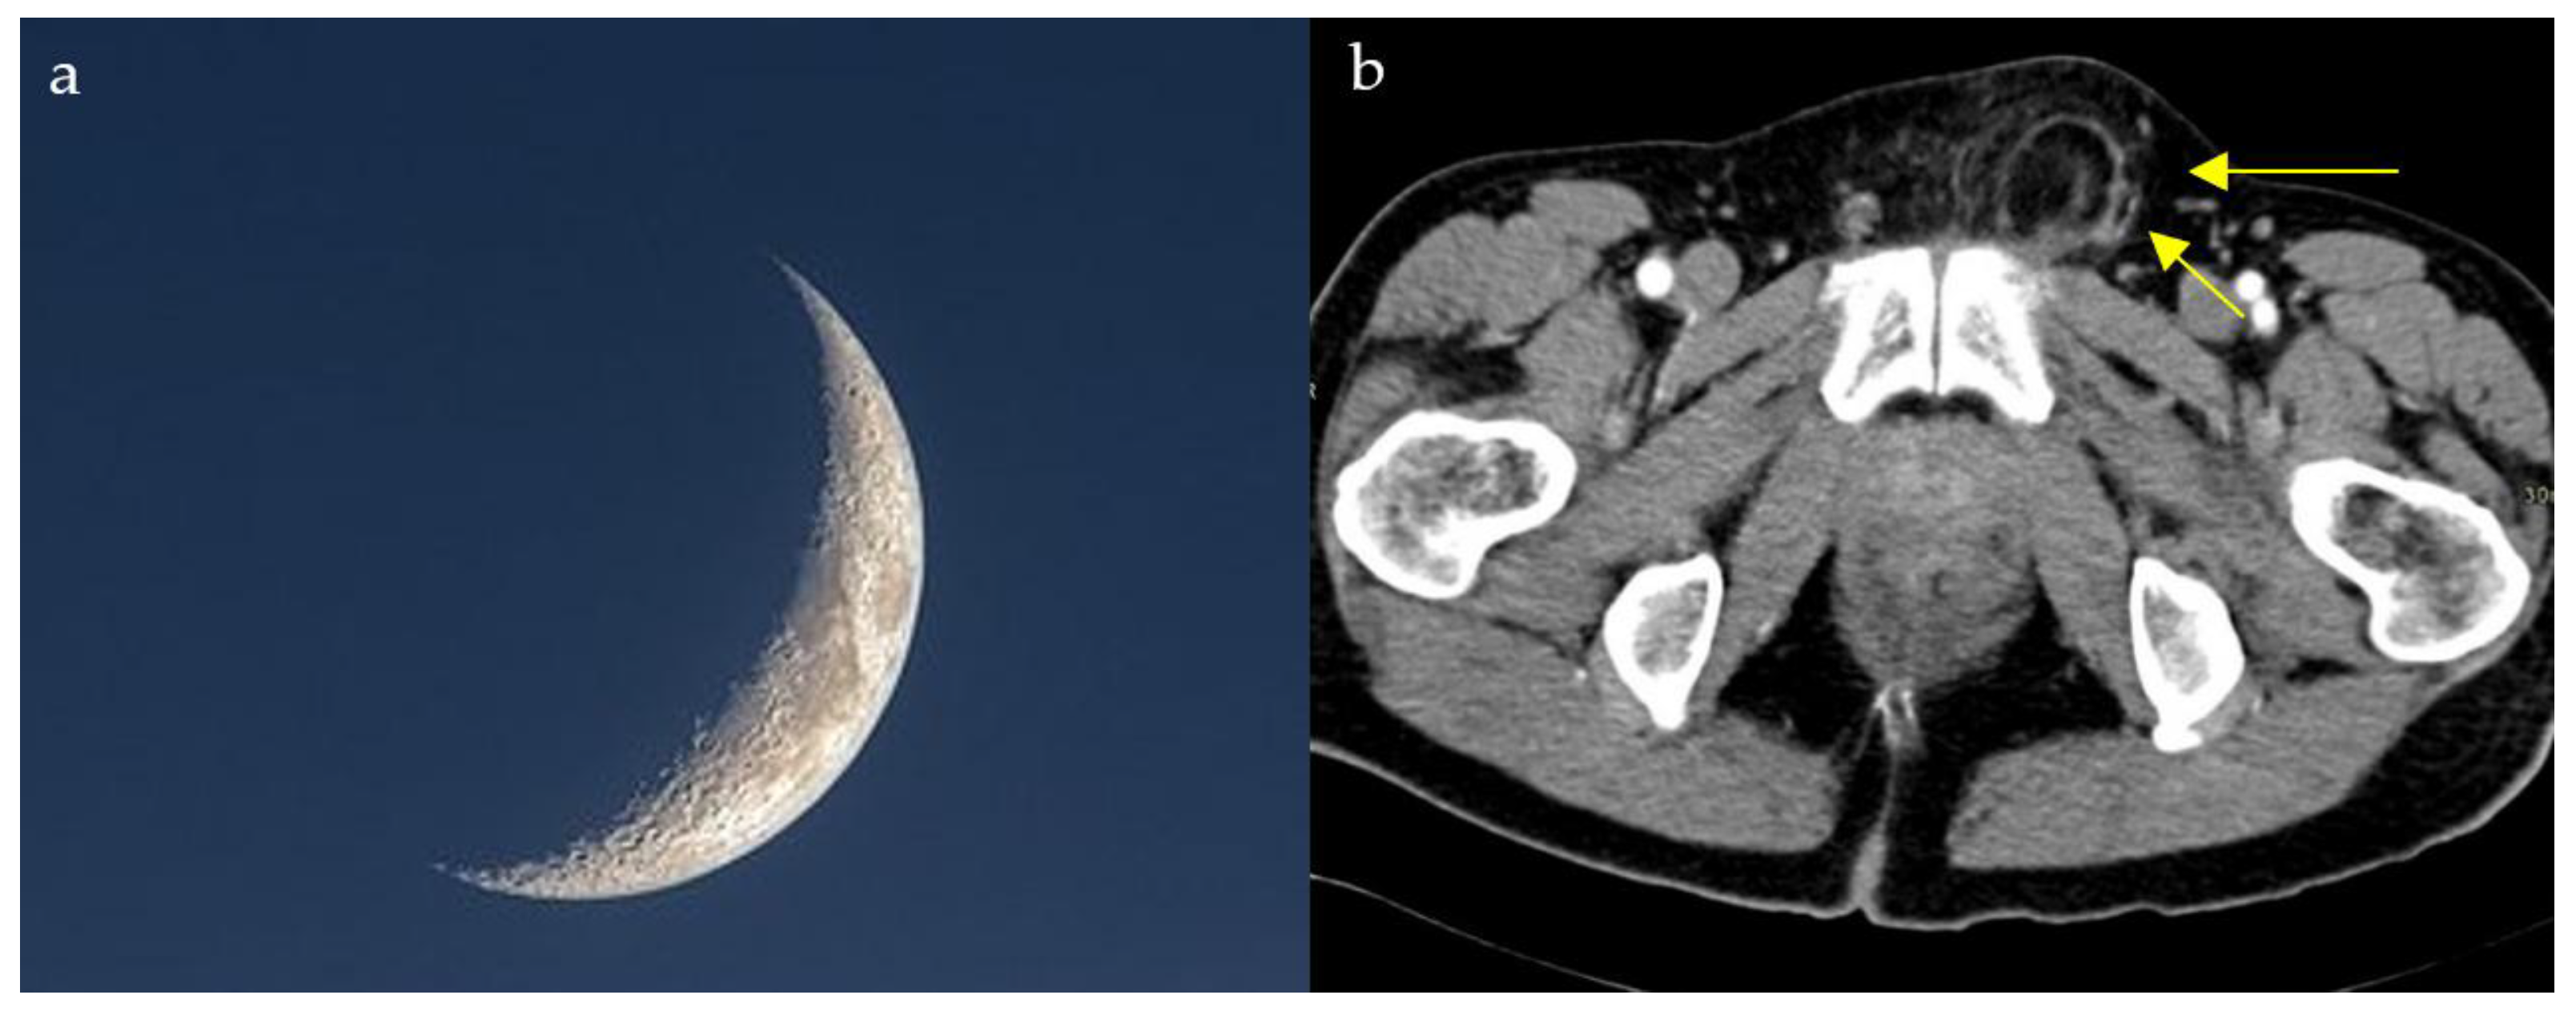

2.5. Milky Way Sign

2.14. Air Crescent Sign